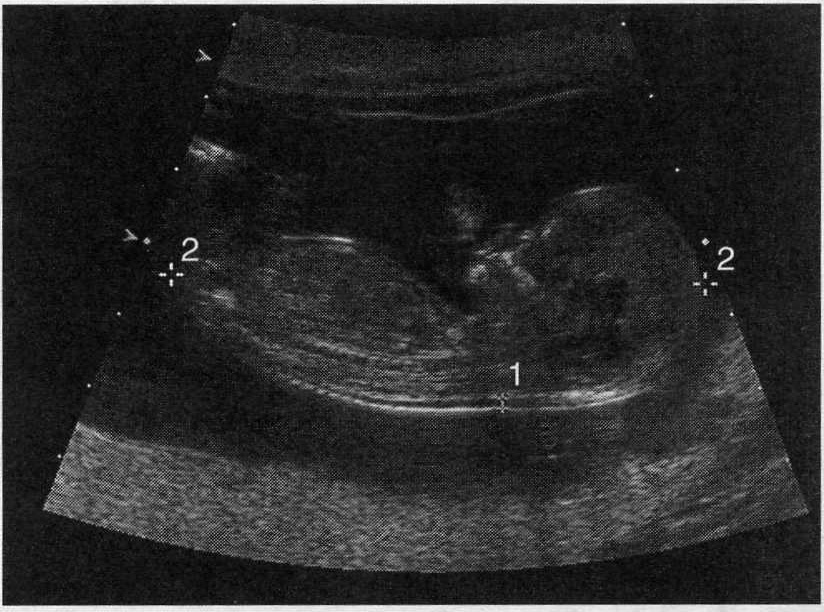

what important fetal measurement does this image demonstrate

crown rump length

name the type of multiple gestatoins you would predict from this image

dichorionic-diamnionic

name the type of multiple gestations demonstrated by this sonogram

monochorionic -diamnionic